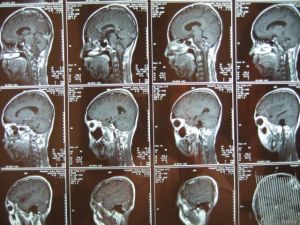

2..頭部CT或MRI